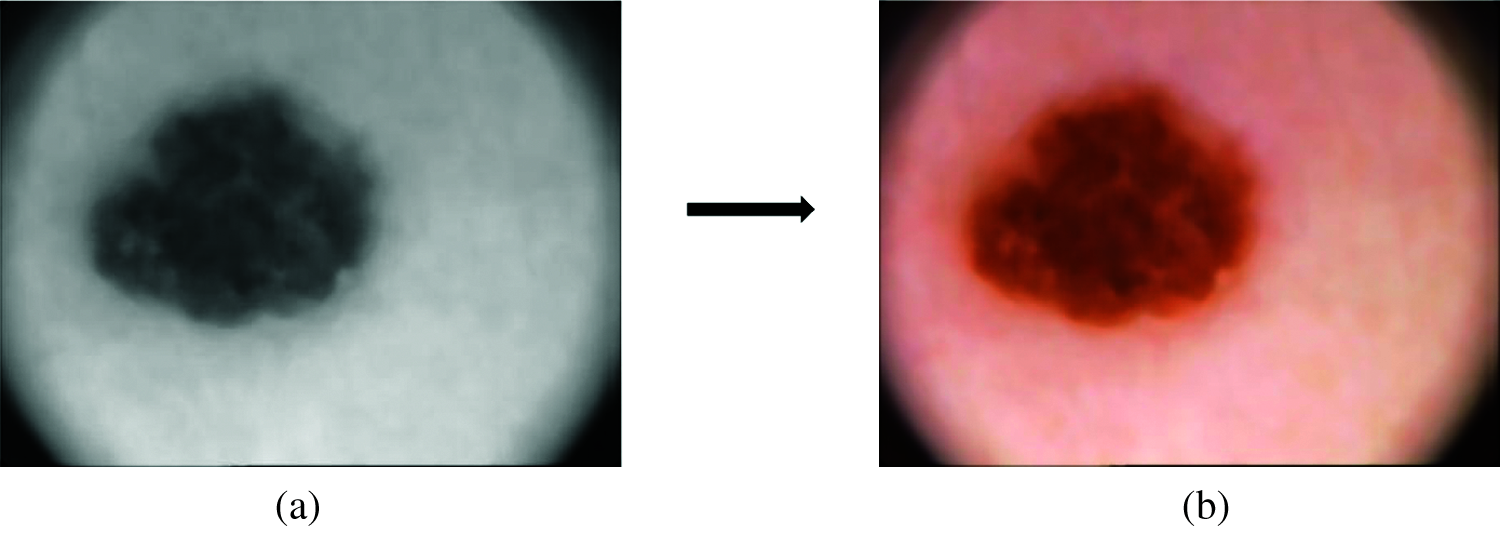

The dermoscopic images consist of noise and hair which has to be removed before feature extraction module step. The noise present in the dermoscopic images is mainly salt & pepper noise and the presence of this noise and hair will affect the overall performance of the system. A non-linear filter is designed in such a way that it should remove both noise and hair from the dermoscopic images. Here, median filtering method is used to remove this unwanted information from the images. The pixels identified by the mask are sorted in the ascending order and the median value is computed and replaced as the center pixel value. Fig. 3 shows samples of images before preprocessing and after preprocessing.

Figure 3: (a) Samples of input images containing noise and hair, (b) output after removing noise and hair